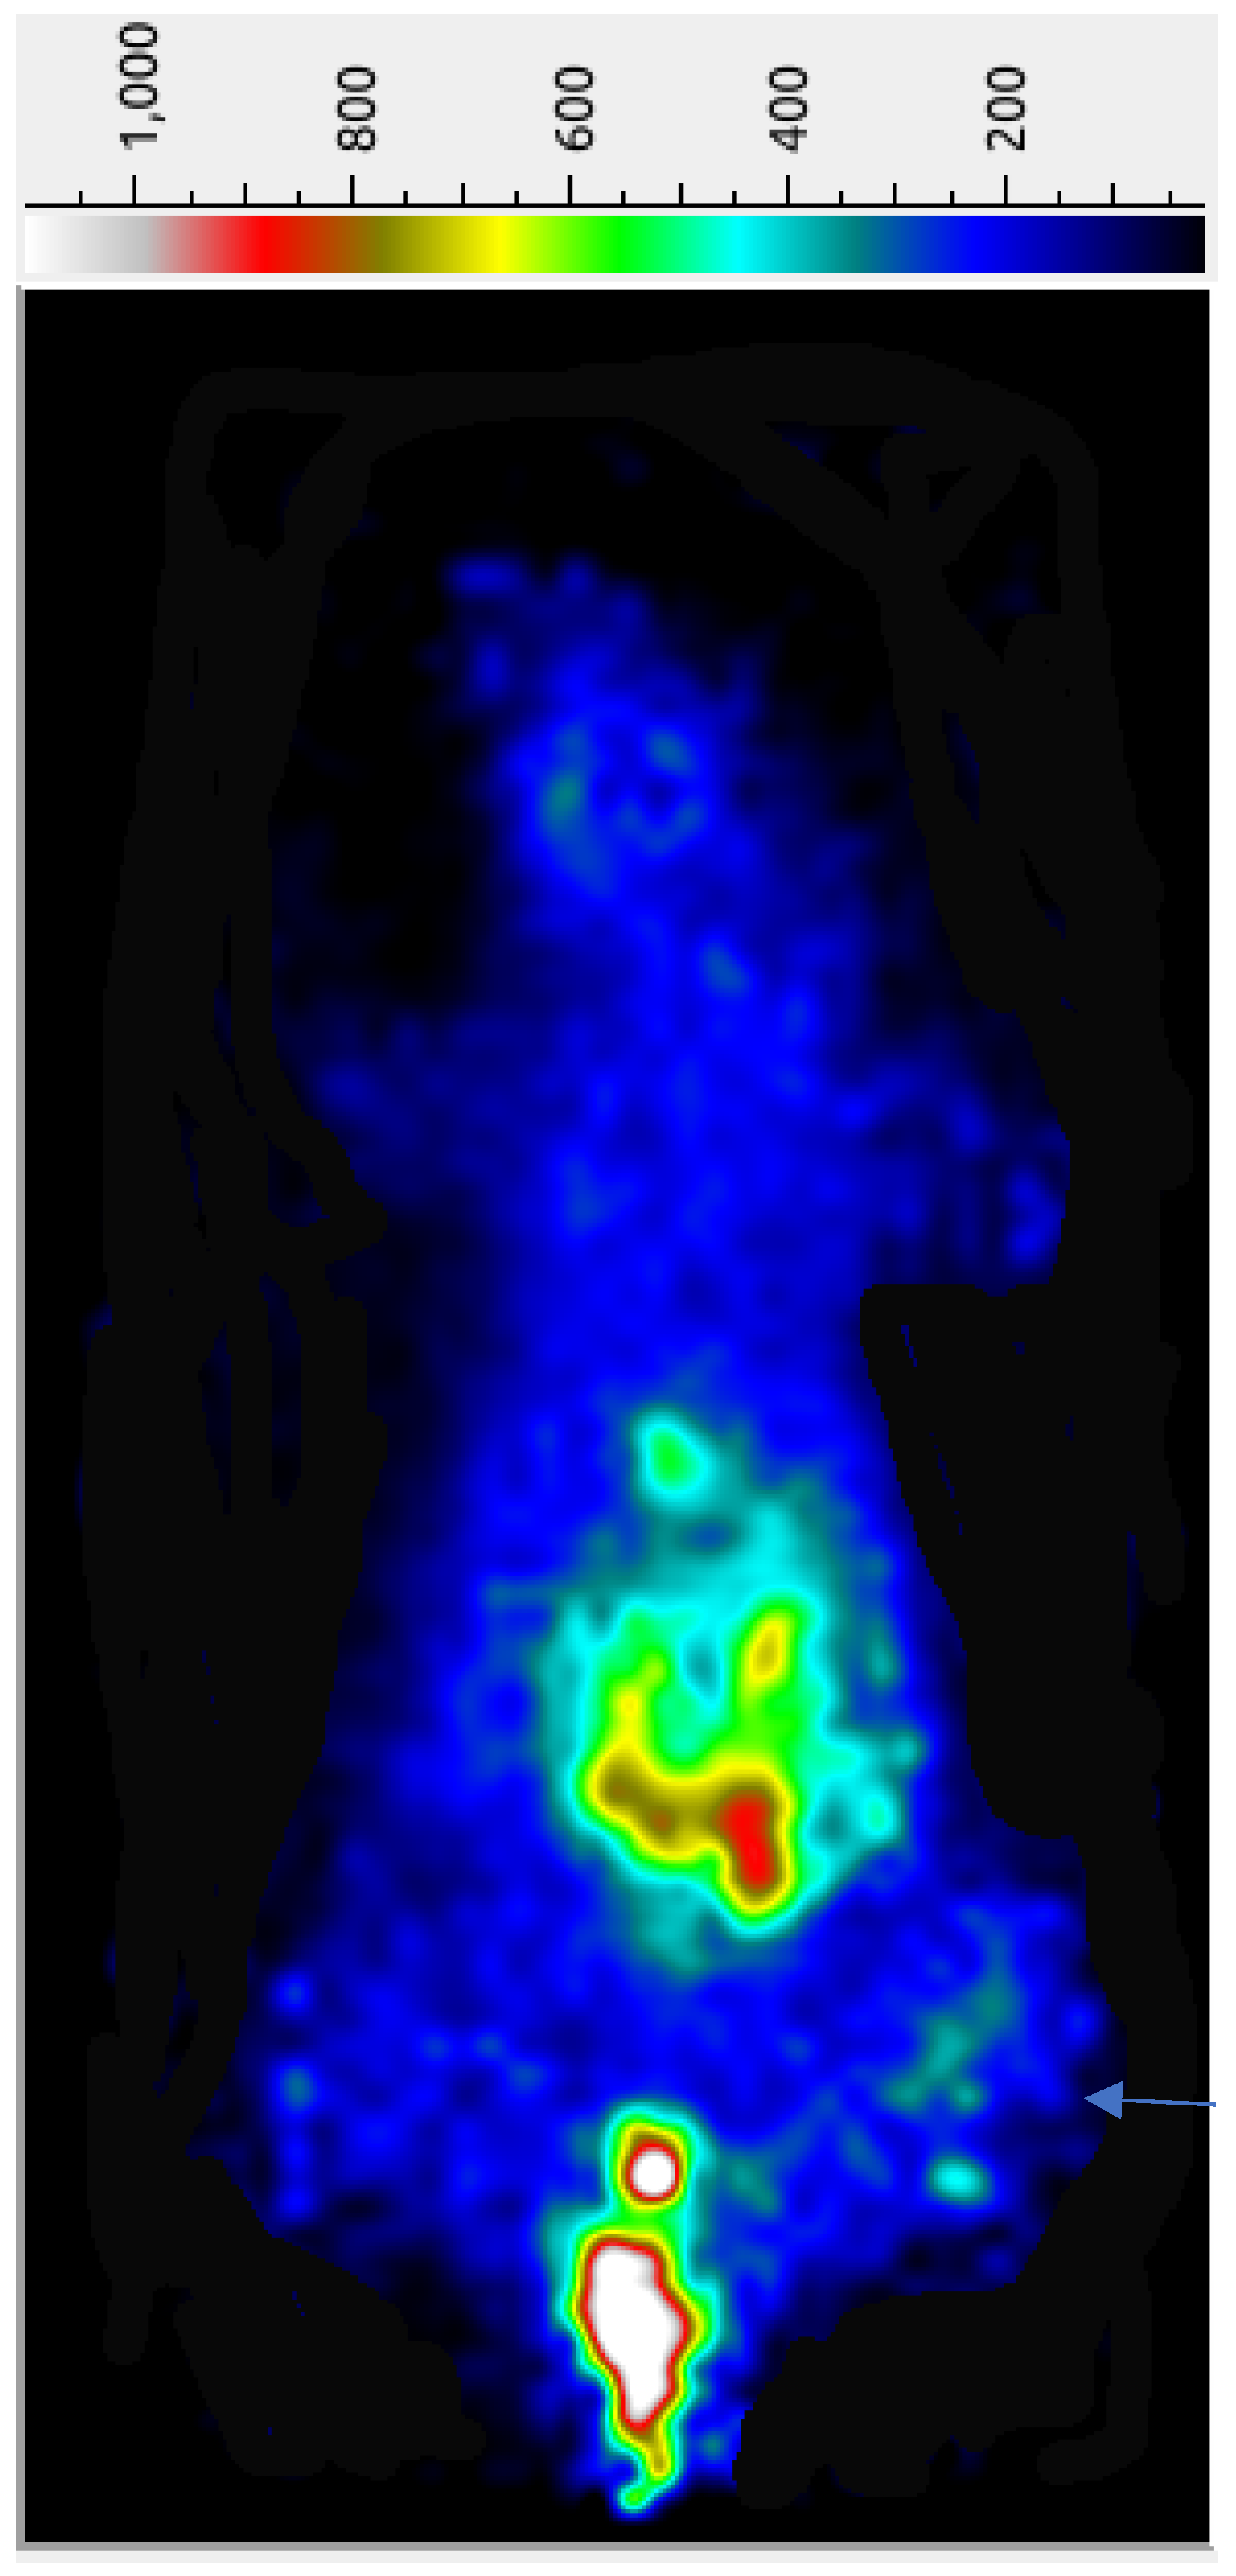

The preliminary tumor imaging potential of the 68Ga-AngII peptide analog was examined in female nude mice carrying subcutaneous triple-negative MDA-MB-231 tumor xenografts at 45 min p.i. While a significant accumulation of radioactivity was seen in the abdominal site together with the urinary bladder, the implanted MDA-MB-231 tumors are reasonably detectable in the PET image (Figure 3), possibly due to the efficient clearance of the radiolabeled peptide from the adjacent organs and tissues. A significantly high urinary bladder radioactivity of 68Ga-AngII peptide analog points out its major excretion pathway. The µPET imaging indicates the potential of the 68Ga-AngII peptide analog to image the AT1 positive tumors. After the imaging study, quantifiable tissue biodistribution was conducted to validate the observations of the PET imaging. The imaging findings were found to agree with the data acquired in quantifiable biodistribution reported in Table 2.

3.9. Micro-PET Imaging

Micro PET imaging was done as described before with minor modifications [19]. To find out the tumor-targeting potential, 68Ga-labeled AngII peptide analog (~1.85–2.78 MBq; 50–75 µCi,100 µL) was administered through the tail vein injection into a nude mouse carrying MDA-MB-231 tumor xenografts. A total of 15 min of static images, with 10 frames (1.5 min each), were obtained in the prone position using a mini PET camera (Bioemtech, Athens, Greece). The PET camera is equipped with a pixelated BGO (bismuth germanate) scintillator and 4 arrays of compact position-sensitive photomultiplier tubes, with a field of view of 48 mm × 98 mm and an intrinsic spatial resolution of ~1.5 mm. The manufacturer preinstalled concurrent image reconstruction software Visual Eyes version 2.01 was used to convert the acquired frames into 2D image visualization. Images were then generated using Image J software version 1.46r (National Institute of Health, Bethesda, MD, USA). Following imaging, animals were dissected and quantitative biodistribution was performed to validate the findings of the PET imaging.

Figure 3. Micro-PETcamera image of a female nude mouse, with MDA-MB-231 breast cancer xenografts, after the tail vein injection of ~75 µCi of 68Ga-DOTA-AngII peptide analog at 45 min post-injection. The arrow indicates the tumor position.